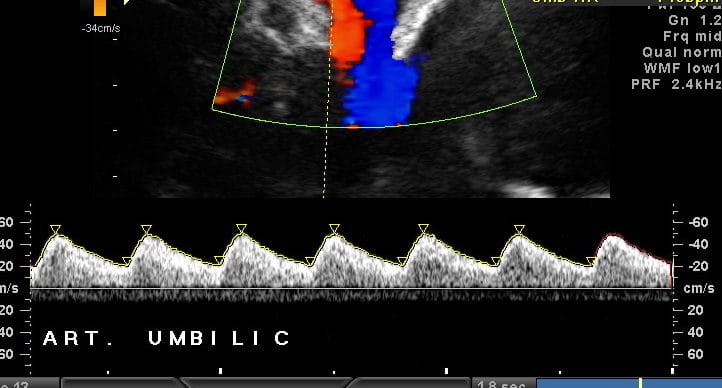

O. Hugh M. Williams S. Turner J. Gardosi > Ultrasound Obstet Gynecol. 2021 Mar;57(3):401-408. doi: 10.1002/uog.22187 Objetivo A detecção pré-natal…